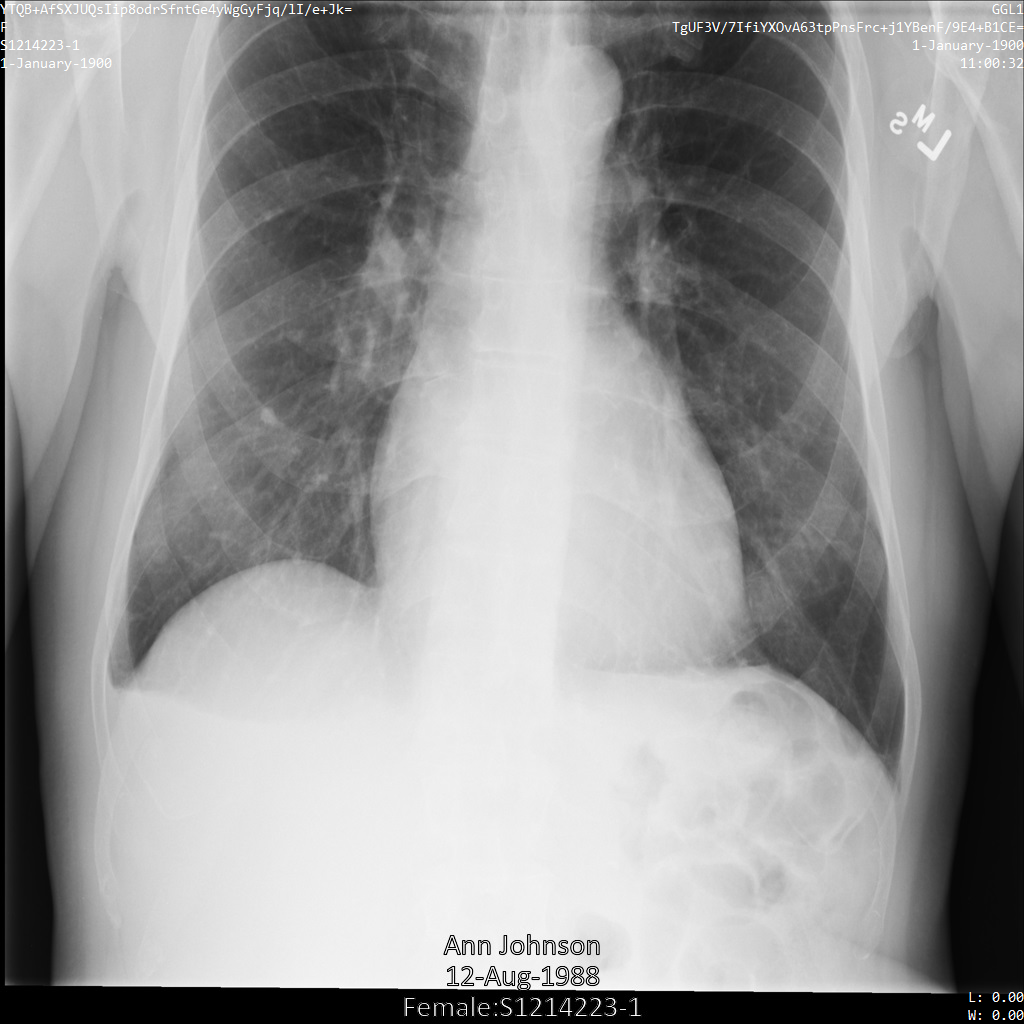

Contoh berikut menunjukkan cara melakukan de-identifikasi set data yang berisi penyimpanan DICOM

dan data DICOM menggunakan profil filter tag ATTRIBUTE_CONFIDENTIALITY_BASIC_PROFILE.

Profil filter tag ini menghapus tag berdasarkan Profil Dasar Kerahasiaan Atribut Standar DICOM.

Setelah mengirimkan gambar ke Cloud Healthcare API menggunakan

profil filter tag ATTRIBUTE_CONFIDENTIALITY_BASIC_PROFILE, gambar akan muncul

seperti berikut. Meskipun metadata yang ditampilkan di sudut atas gambar telah disamarkan, PHI yang tercetak di bagian bawah gambar tetap ada.

Untuk menghapus teks sisipan juga, lihat

Menyamarkan teks sisipan dari gambar.